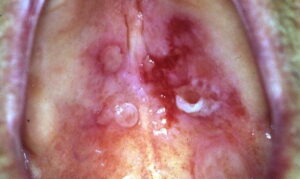

Ocular involvement in patients with cicatricial pemphigoid is common and may become sight threatening  Ocular lesions typically manifest as conjunctivitis that progresses insidiously to scarring. Early ocular disease can be quite subtle and nonspecific. Although disease is usually bilateral, it often begins unilaterally and progresses to both eyes within several years. Patients may complain of burning, dryness, or a foreign-body sensation in one or both eyes; frank blisters on conjunctival surfaces are rarely seen. Early disease is best appreciated by slit-lamp examination. Because disease may be localized to the upper tarsal conjunctiva, it may escape detection without eversion of the eyelids. Chronic ocular involvement can result in scarring characterized by shortened fornices, symblepharons (i.e., fibrous tracts between bulbar and palpebral conjunctival surfaces), and, in severe disease, ankyloblepharons (i.e., fibrous tracts fusing the superior and

inferior palpebral conjunctivae with obliteration of the conjunctival sac). Conjunctival scarring also can cause entropion and trichiasis (i.e., in-turning of the eyelashes) that result in corneal irritation, superficial punctate keratinopathy, corneal neovascularization, corneal ulceration, and/or blindness. Additional ocular complications include scarring of the lacrimal ducts, decreased tear secretion, and loss of mucosal goblet cells leading to decreased tear mucus content and unstable tear films. It is very important for patients with suspected ocular involvement to be examined by an ophthalmologist, because early disease may be subtle, is only identified by slit-lamp examination, and can result in severe complications. Cicatricial pemphigoid may be limited to the eyes.